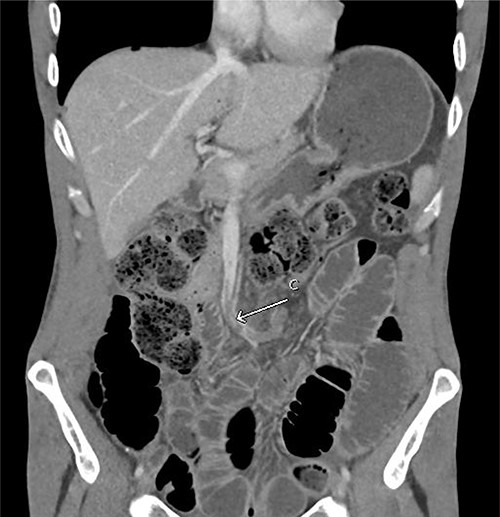

His admission was further complicated by acute kidney injury (AKI) secondary to high nasogastric + stoma outputs (6.6 L/day at peak) requiring aggressive fluid replacement and Loperamide + Metamucil. This was likely contributed by the relatively proximal nature of the stoma. Repeat CT also showed a thrombus within the left-sided branches of the superior mesenteric vein continuing into the vein proper (Fig. 2), which was managed as a provoked venous thromboembolism event with 6 months of therapeutic anticoagulation. Given prolonged malnutrition, a peripherally inserted central catheter was also inserted for total parenteral nutrition. Patient was discharged from ICU on Day 5 and had a total of 27 days in hospital with a normalized stoma output, resolved AKI and education to facilitate community management of stoma.

Repeat CT abdomen pelvis with contrast in the portal venous phase showed (C) filling defect in the superior mesenteric vein. Multiple dilated small bowel loops without a clear transition point were also evident, suggestive of ileus.